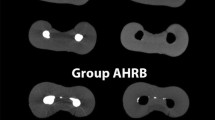

CBCT images of the multi-filament GFRC post to dentin after invasive sha** of the tooth root canal are shown in Fig. 9. Before cementation, there is still noticeable space at the coronal third of the multi-filament GFRC post to dentin region although the apical third region was partially filled with the GFRC filaments.

Microscopic images of the interfaces involving dentin, resin-matrix cement, and multi-filament GFRC post can be seen in Fig. 10. It can be seen the GFRC filaments are distributed in the tooth root canal. However, the resin-matrix cement volume was high among the filaments that increased the presence of defects and macro-scale voids as seen in Fig. 10A–C.

Considering the tooth mesial side, standard sha** of tooth root canals provided shorter distances from the GFRC post to the intracanal dentin surfaces when compared to the invasive one (Fig. 6A). In the distal view, the standard sha** showed higher mean values on the distance from the GFRC post to the remaining intracanal dentin at the coronal measurement of the tooth although revealed quite lower values at the apical and middle thirds (Fig. 6B). On the tooth buccal side, the invasive sha** at all different thirds revealed high values of distance from the GFRC post to the remaining intracanal dentin when compared to the standard preparation. However, there were no statistical differences in the invasive sha** at the apical and middle third of the tooth (Fig. 6C). Also, a multi-filament GFRC post revealed misfit of filaments mainly at the coronal third as seen in Fig. 9 and therefore there are limitations regarding the number and diameter of filaments.

After invasive sha**, the fitting of the standard or multi-filament GFRC post is compromised that increases the occurrence of spaces from the post to the intraradicular dentin surfaces mainly at the coronal third. Spaces are filled by resin-matrix cements on cementation although thick resin-matrix cement layers increase the probability of defects (i.e., cracks and pores) and stress concentration leading to catastrophic fractures. The fitting of multi-filament GFRC posts has limitations regarding the number and diameter of filaments. Thus, the volume of resin-matrix cement around multi-filament GFRC posts varies among the filaments.